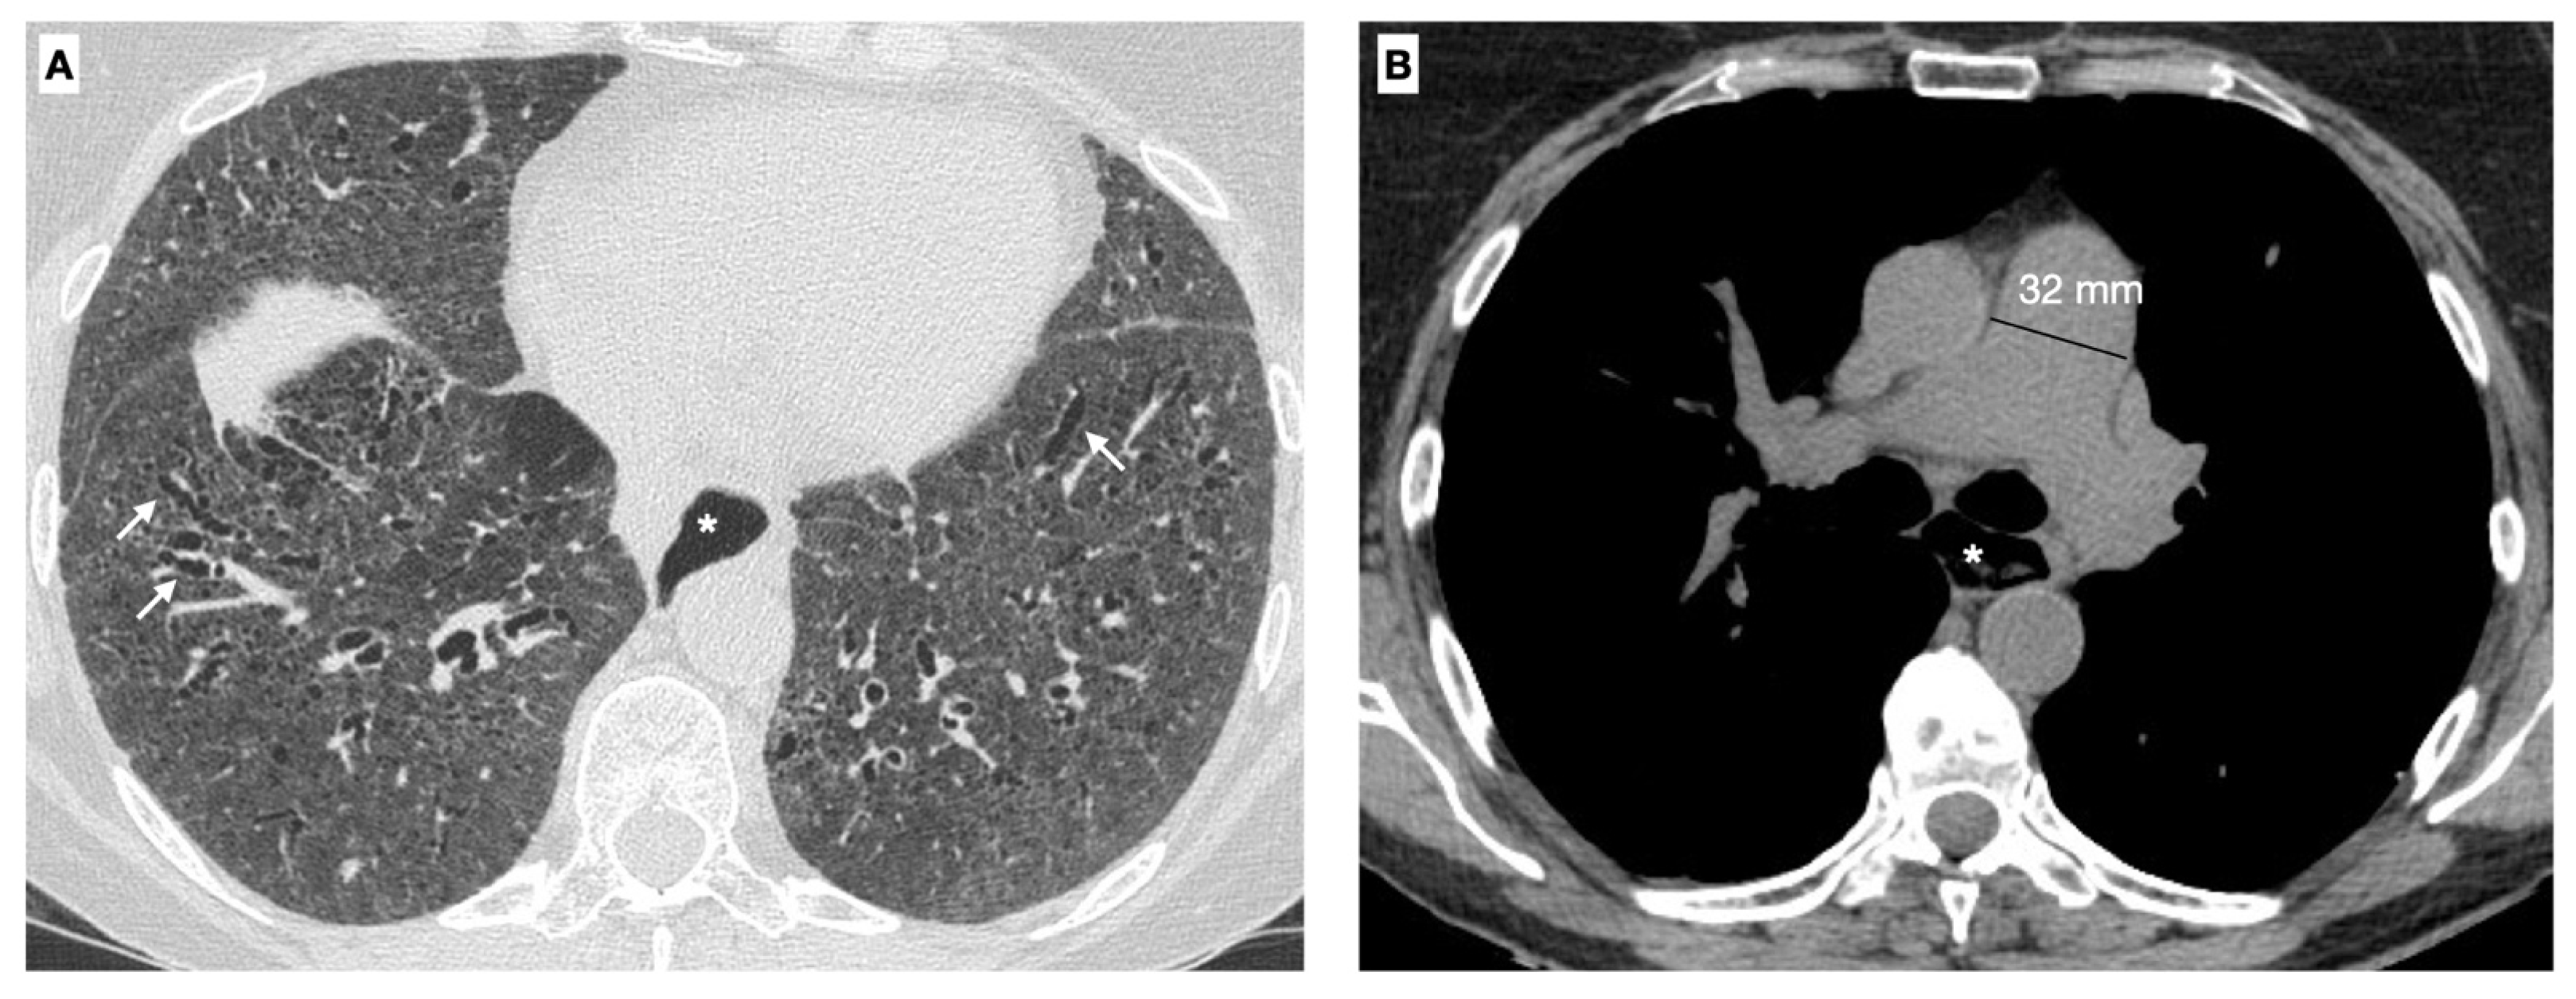

- Goldin, J.G.; Lynch, D.A.; Strollo, D.C.; Suh, R.D.; Schraufnagel, D.E.; Clements, P.J.; Scleroderma Lung Study Research Group. High-resolution CT findings in patients with symptomatic scleroderma-related interstitial lung disease. Chest 2008, 134, 358–367. [Google Scholar] [CrossRef] [PubMed]

- Temiz Karadag, D.; Cakir, O.; San, S.; Yazici, A.; Ciftci, E.; Cefle, A. Association of quantitative computed tomography ındices with lung function and extent of pulmonary fibrosis in patients with systemic sclerosis. Clin. Rheumatol. 2022, 41, 513–521. [Google Scholar] [CrossRef]

- Ruaro, B.; Baratella, E.; Confalonieri, P.; Confalonieri, M.; Vassallo, F.G.; Wade, B.; Geri, P.; Pozzan, R.; Caforio, G.; Marrocchio, C.; et al. High-Resolution Computed Tomography and Lung Ultrasound in Patients with Systemic Sclerosis: Which One to Choose? Diagnostics 2021, 11, 2293. [Google Scholar] [CrossRef]